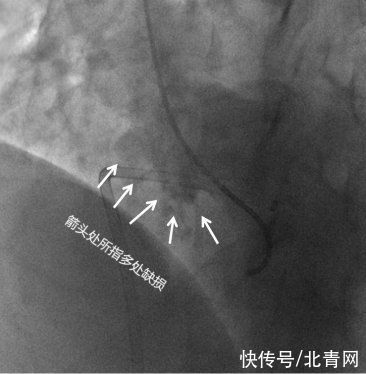

陈某室间隔上的5个孔洞

心脏里竟然5个洞

从医20多年医生都说极少见

手术难度也极高